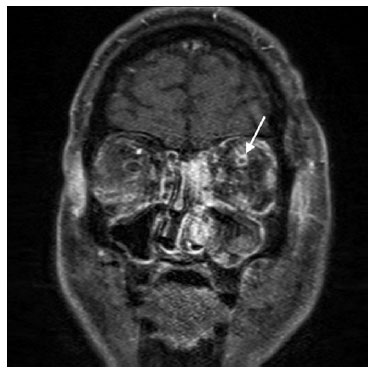

At five days, the patient agreed to undergo magnetic resonance imaging and venography (MRV), which revealed thromboses in the bilateral cavernous sinus (worse in the left eye), left superior ophthalmic vein, and right inferolateral orbital vein (Figures 1 and 2), for which heparin therapy was initiated. Blood cultures revealed methicillin-resistant Staphylococcus aureus. Therefore, cefepime was switched to ceftaroline for enhanced central nervous system penetration.

02-fig01.jpg)